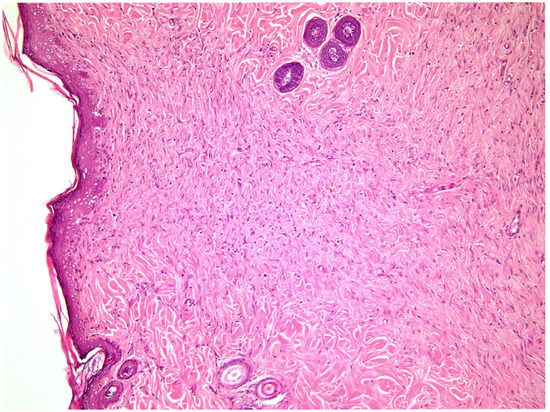

2.2. Histological Study

—fibrin clot,

—granulation tissue,

—adipose tissue.